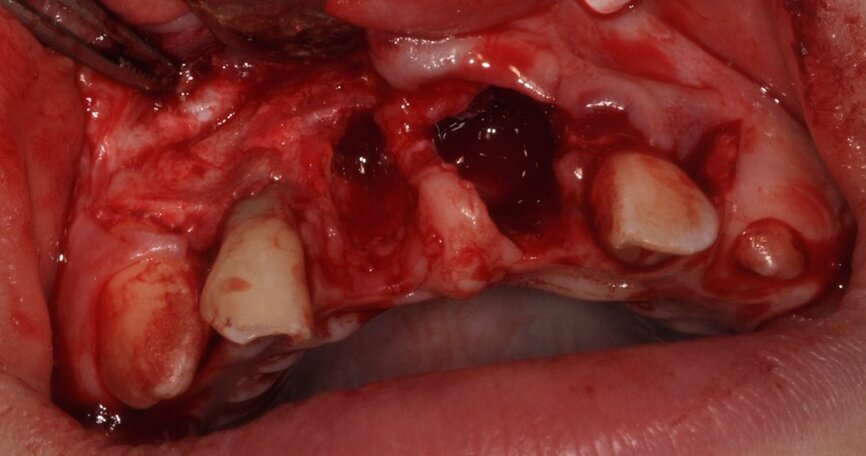

W znieczuleniu nasiękowym 1 amp. 4% Ubistesin Forte nacięto i odwarstwiono płat trapezowy śluzówkowo-okostnowy w okolicy 13 do 23. Zęby 11 i 21 usunięto w całości (Ryc. 3 i 4). Wykonano ablację kości laserem Er:YAG (LightWalker® Fotona®), (2 W, 10 Hz, 200 mJ, QSP) usuwając ziarninę zapalną, a następnie laserem Nd:YAG (LightWalker®, Fotona®), (1,5 W, 10 Hz, MSP) przeprowadzono redukcję bakterii (Fotona®).

Ryc. 4¬_Stan miejscowy po ekstrakcji i ablacji kości.